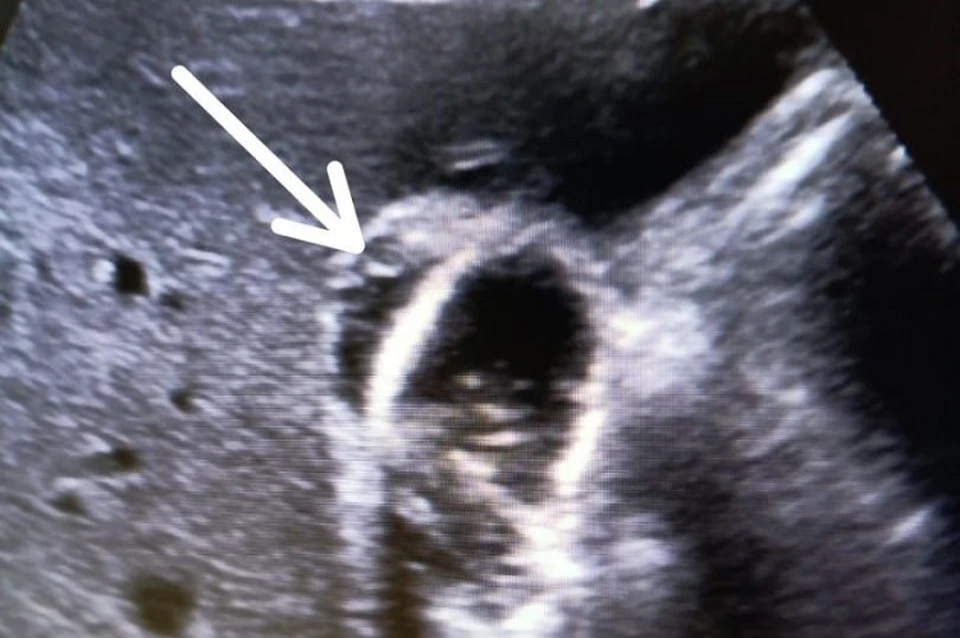

Частичный отрыв желчного пузыря — опасное состояние. Фото: минздрав СК

Они выбрали щадящий подход: регулярно проводили УЗИ, следили за анализами крови, а также прописали антибиотики для профилактики инфекций и гемостатические препараты для остановки кровотечения.